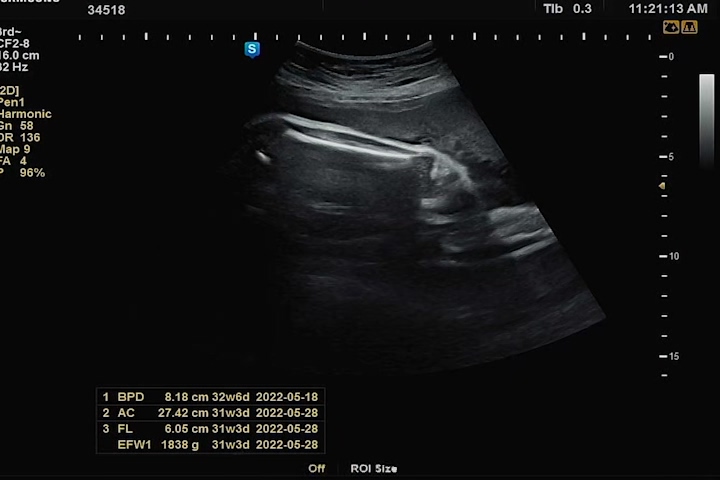

두 손으로 얼굴을 가리고 있어서 얼굴 윤곽이 또렷이 나오진 않았지만, 그래도 눈 뜨고 하품도 하고 해서 너무나 귀여웠다. 이전 기록과 비슷하게 주수에 비해 머리둘레는 살짝 크고, 배 둘레, 다리 길이, 체중은 살짝 미달이었다. 체중도 1.8kg 평균주수 대비 살짝 적지만 작은 아가로 태어날거라 생각한다. 그래도 까꿍이 3kg는 찍자꾸나! 화이팅!!!!

큰 편차가 아니라 미비한 편이어서 꾸준이 아내가 잘 챙겨 먹고 잠도 많이 자면서 휴식하면 건강하게 태어나지 않을까 싶다 :)